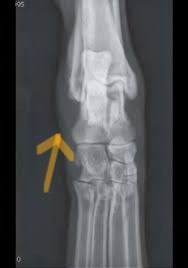

Mild cases will have swelling of the affected joint on palpation and discomfort with manipulation. Moderate to severe cases can have a visible loss of the upright carriage of the wrist or ankle with palpable instability. X-rays will show soft tissue swelling around the affected joint. The joints will ‘open up’ when pressure is placed to test the areas of concern. It is very important to identify at what level within the wrist or ankle the damage is present and if there is an associated fracture because this can change what procedure is recommended.

X-rays will demonstrate the soft tissue swelling. The instability can also be demonstrated with stressed views. In severe cases, a complete luxation may be present.